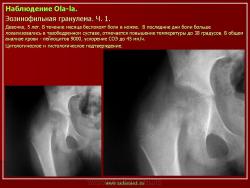

Из опубликованных наблюдений н сайте.